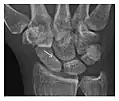

High-energy trauma fractures

Occult osseous injuries may result from a direct blow to the bone by compressive forces of adjacent bones against one another or by traction forces during an avulsion injury. Lesions in the tibial plateau, hip, ankle, and wrist are often missed. In a tibial plateau fracture, any disruption of the posterior and anterior cortical rims of the plateau should be sought. Impaction of subchondral bone will appear as an increased sclerosis of the subchondral bone (Figure 1). In the hip, posterior acetabular fractures also present subtle radiographic findings. The acetabular lines should then be carefully examined keeping in mind that the posterior rim, which is harder to see on X-rays, is more frequently fractured than the anterior rim (Figure 2). In the wrist, detection of carpal bone fractures is often challenging, with up to 18% of scaphoid fractures radiographically occult. Carpal fractures, especially the scaphoid, are associated with the risk of avascular necrosis. In apparently normal wrist radiographs from symptomatic patients, if there is history of a fall on an outstretched hand with pain in the anatomic snuffbox, suggesting scaphoid injury, the initial examination with posteroanterior, lateral, and pronation oblique views must be complemented by other specific views such as supination oblique and the "scaphoid" view A careful examination of cortices for evidence of discontinuity or offset and cancellous bone for lucency is necessary (Figure 3).[1]

-

a -

b -

c

Figure 3: A 26-year-old man presenting with wrist pain after being assaulted. (a) Initial anteroposterior radiograph shows a subtle linear lucency within the scaphoid extending to the scaphocapitate articular surface that was overlooked (arrow). (b) Initial "scaphoid" view was negative. (c) Followup anteroposterior radiographs, 12 days later, shows obvious scaphoid fracture (arrows).[1]